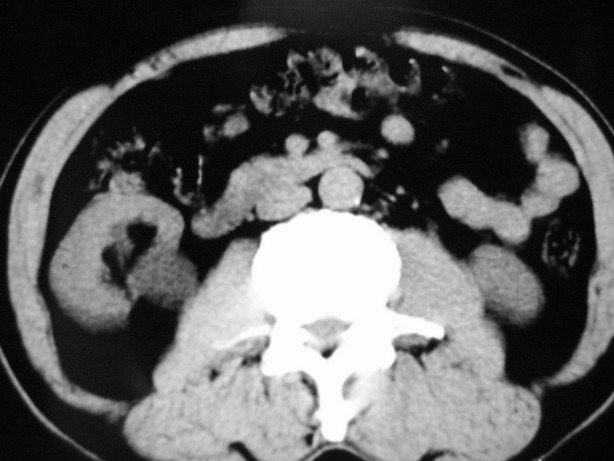

收集期:

延迟期造影剂没有进入囊性病灶内考虑多发性肾囊肿,包括一个盂旁囊肿。

肾盂旁多囊性占位,有实性成分,增强有轻度强化,收集期病变内无造影剂显影。诊断肾盂旁囊肿,有实性成分无法解释,查书后诊断为:多房性囊性肾瘤!!不知大家同意否?????????对本病知道不多,望大家不吝赐教!!